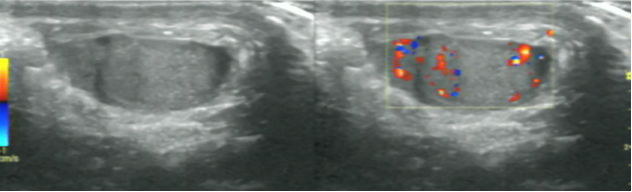

急性睾丸附件扭转,是小儿泌尿系统常见急症之一,常见于8-13岁的患儿,是引起小儿急性阴囊疼痛的主要因素,左侧较右侧发生率高,成年人极少见,症状酷似睾丸扭转,易与急性睾丸附睾炎和睾丸扭转相混淆,术前诊断率<20%。超声诊断是睾丸附件扭转首选检查。